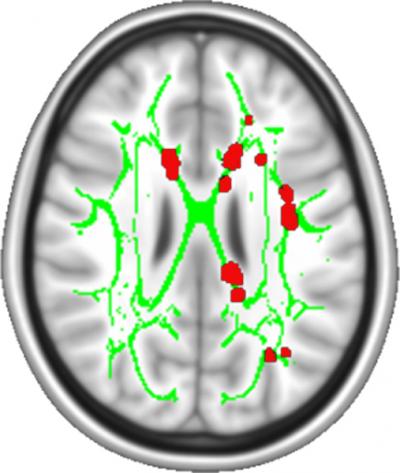

In this study, the researchers used a scanning technique called diffusion tensor imaging (DTI) which measures the structure of white matter, the nerve cell wires, or axons, which connect brain cells in different parts of the brain. They found a consistent difference in white matter between the subjects who recovered and the subjects who experienced pain throughout the year.

In agreement with this idea, the researchers also found that the white matter of subjects who had persistent pain looked similar to a third group of subjects known to suffer from chronic pain. In contrast, the white matter of the subjects who recovered looked similar to that of healthy control subjects.

To test this idea further, the researchers asked whether the white matter differences they saw during the initial brain scans predicted whether the subjects would recover or continue to experience pain. They found white matter brain scans predicted at least 80 percent of the outcomes.

The nucleus accumbens and the medial prefrontal cortex are two brain regions thought to be involved with pain. Further examination of the brain scans suggests that the white matter structure connecting these brains regions is different between the subjects who recovered and those who had persistent pain.